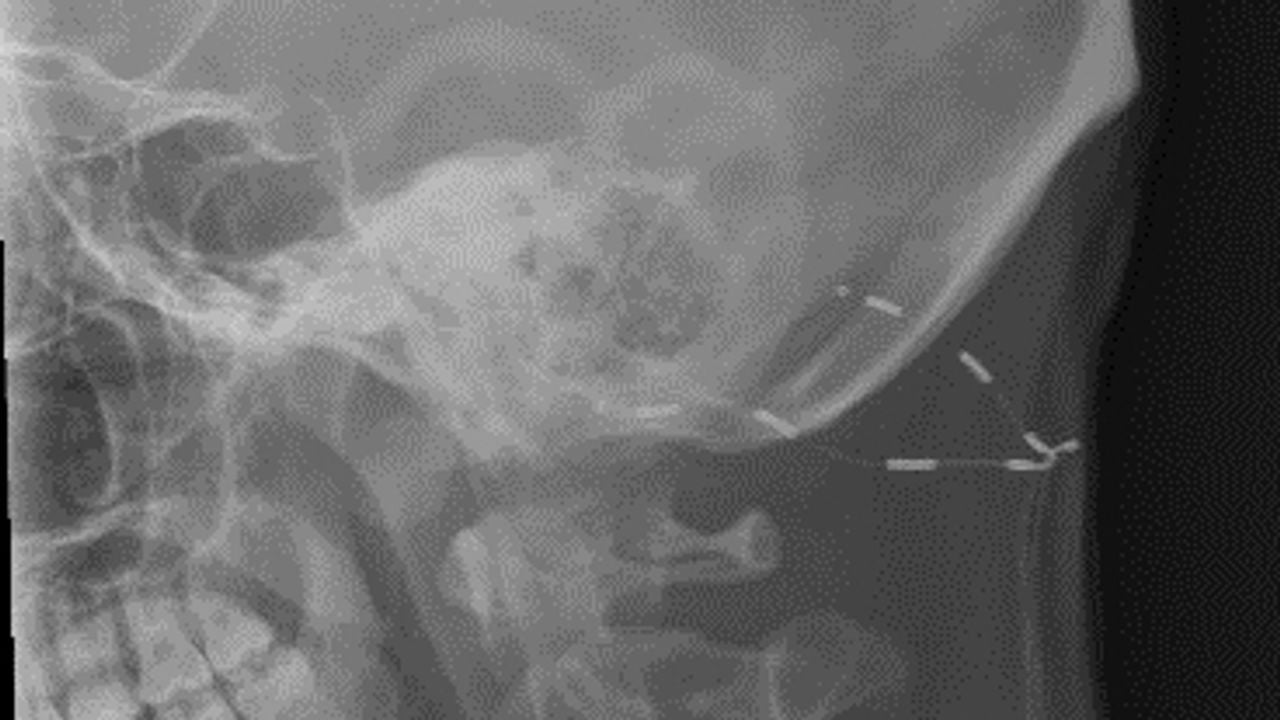

Toen kwam de redding. In januari kwam hij in aanmerking voor een behandeling: er werd een neurostimulator in zijn hoofd geplaatst die lichte stroomstootjes geeft aan bepaalde zenuwen in het hoofd. “De ziekte is daarmee niet weg, maar de aanvallen zijn een stuk draaglijker.”